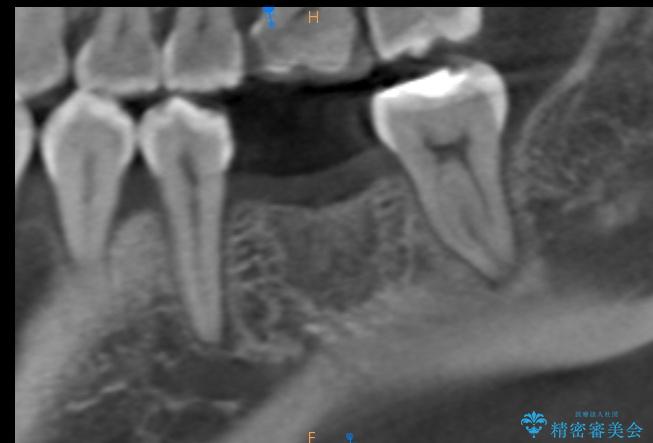

治療計画を立てる上で詳しく精密検査をしたところ、左下の6番目の歯につきまして治療が必要な状態であることが分かり、かぶせ物を外し、内部を確認しました。

結果としては深い部分で根が破折してしまっていました。